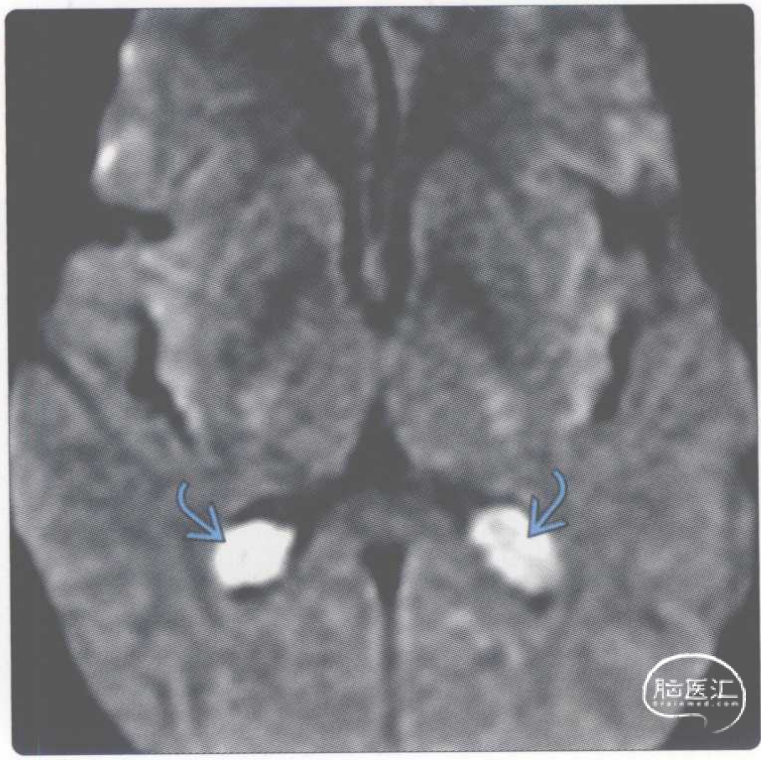

【影像时间·264】一例脉络丛囊肿患者